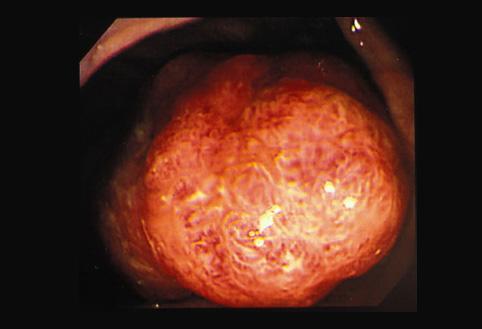

A case of adenoma occurring in the inverted appendix which intussuscepted into the ascending colon.

[ Image ID:9492 ]

Tumor-like lesions/Others

Large intestine(Colon)/Appendix

Endoscopy

40 -